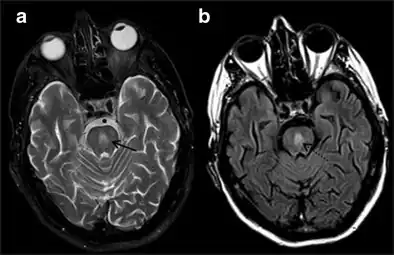

It can be diagnosed clinically in the appropriate context, but may be difficult to confirm radiologically using conventional imaging techniques. Changes are more prominent on MRI than on CT, but often take days or weeks after acute symptom onset to develop. Imaging by MRI typically demonstrates areas of hyperintensity on T2-weighted images.[29]

-

Central Pontine Myelinolysis -a & b) axial T2W and FLAIR images at the level of pons show central pontine hyperintensity -